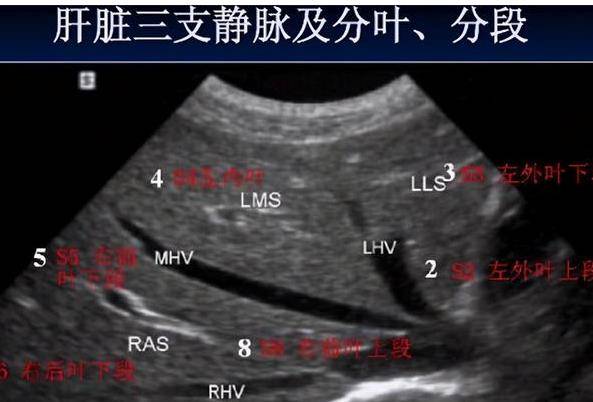

B超利用超声波成像 , 安全没有辐射 , 价格相对来说比较便宜 , 虽然各地区有差异 , 但一般都在100元左右浮动 , 即便多次检查也不会带来很大经济负担 。 而且腹腔器官因紧挨胸腔 , 受呼吸影响大 , CT检查容易受到影响 , 而超声不会 。 同时 , 超声对肝脏、脾脏、胰腺等腹腔脏器诊断准确率较高 。

正常情况下 , 一般的常规例行体检、或者只是查查有脂肪肝到什么程度 , 可以进行简单的B超检查 , 花钱买个放心 。 如果患者或是慢性乙型肝炎、丙型肝炎的随诊检查 , 或者是既往发现过肝囊肿、肝血管瘤 , 医生说不要做手术、随诊 , 这种情况下的随诊检查也只需要检查超声就可以了 。

一般B超检查都能满足临床需求 , 但是超声受气体干扰很大 , 如果肠道含气多或进食后都会影响肝胆系统的检查的准确性 , 所以查腹部的B超要空腹 , 即8小时内不进餐 , 服用常规的药物及服药饮水是可以的 。

如果用食物打个比方 , B超像挑西瓜前敲一敲一样 , 边敲边看病灶情况 。 而CT检查就像切火腿 , 切成薄片一层一层显示到底哪片火腿上面肉多 , 薄层CT扫描 , 精细到4mm层厚 , 微小的病灶都能发现 。

如果B超显示异常 , 需要进一步明确性质及病变的部位与周围组织的关系、血供的情况等 , 就可以进行CT检查 , 有助于确诊 。 特别是怀疑恶性的 , 通过CT可以鉴别 , B超一般不用于癌症的筛查 。 如果同时伴有右侧肋部不舒服的症状 , 有面色发黄、周身皮肤黄疸、出血不易停止、尿色发红疑似肝病症状的 , 化验血合并肝功能异常的 , 一般医生都会建议查肝脏CT进一步明确诊断 。